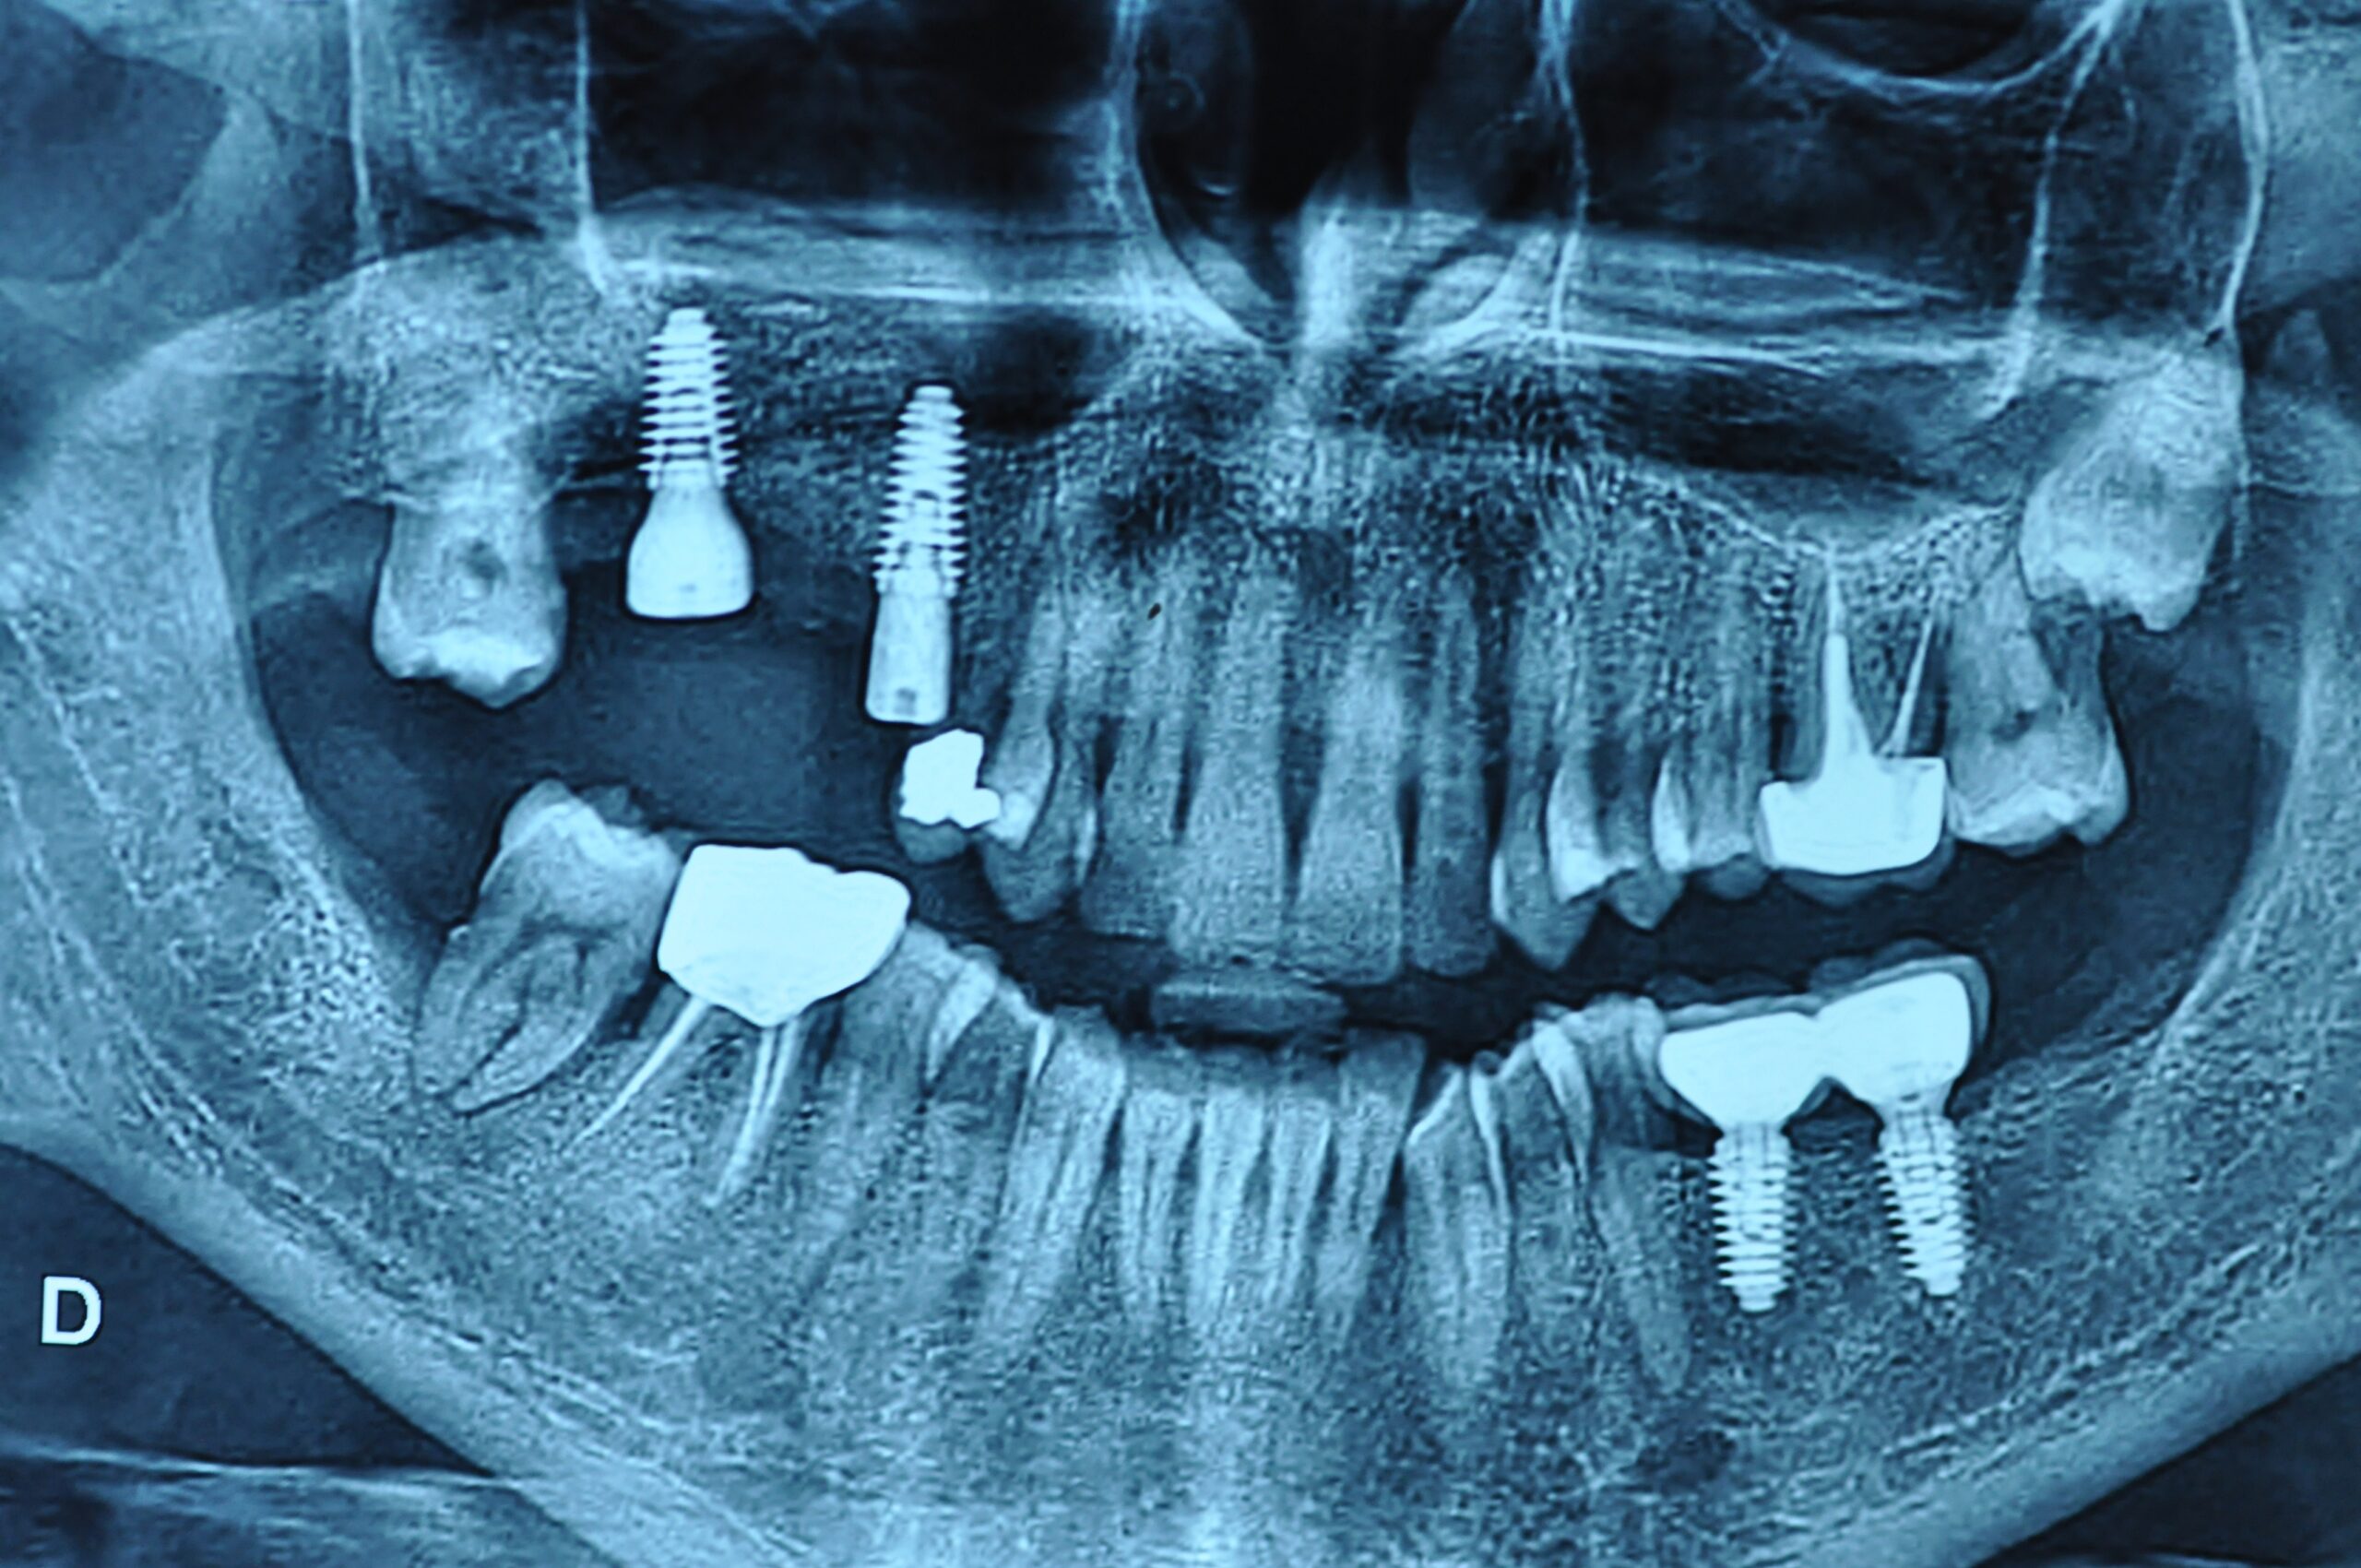

Un implant dentaire est une racine artificielle en titane qui remplace la racine manquante d’une dent naturelle. Il est placé dans la mâchoire inférieure ou supérieure pour remplacer une ou plusieurs dents. Après la période de cicatrisation osseuse, la couronne est fixée au-dessus de l’implant.

La pose d’un implant dentaire s’effectue en plusieurs étapes étalées sur quatre à neuf mois, et en règle générale, de la façon suivante :

Durant cette étape, le praticien pose les implants dentaires pour remplacer les racines manquantes. À l’issue de cette intervention, vous sentirez des implants couverts par la gencive, et qu’ils sont mis en “nourrice” : cela permet à l’os de cicatriser autour des implants.

La durée totale du traitement dépend de plusieurs facteurs. Il est déterminé en fonction du nombre de dents à remplacer, du volume osseux, de l’état général du patient. En général, il faut entre 3 et 9 mois.